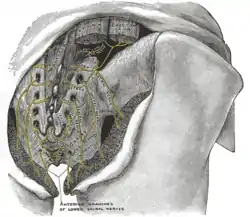

The posterior divisions of the sacral nerves.

The posterior divisions of the sacral nerves.